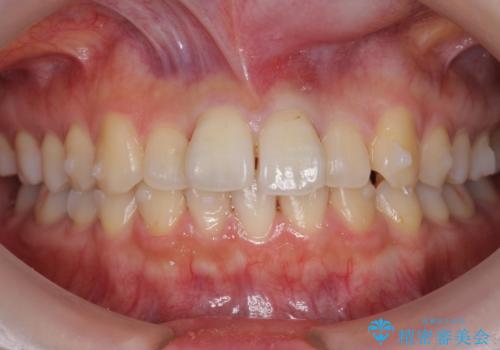

軽度の前歯のがたつき 下の前歯が生まれつき少ない

- 前歯のがたつきを主訴に来院。

下の前歯が生まれつき3本でした。

そのため、上の前歯が少し余るような形で出っ歯になっていたため、スペースを作って引っ込めています。